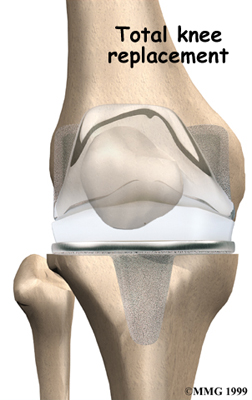

Artificial Knee Replacement

An artificial knee replacement is the ultimate solution for advanced knee OA.

Surgeons prefer not to put a new knee joint in patients younger than 60. This is because younger patients are generally more active and might put too much stress on the joint, causing it to loosen or even crack. A revision surgery to replace a damaged prosthesis is harder to do, has more possible complications, and is usually less successful than a first-time joint replacement surgery.

Related Document: FYZICAL East Asheville's Guide to Artificial Joint Replacement of the Knee